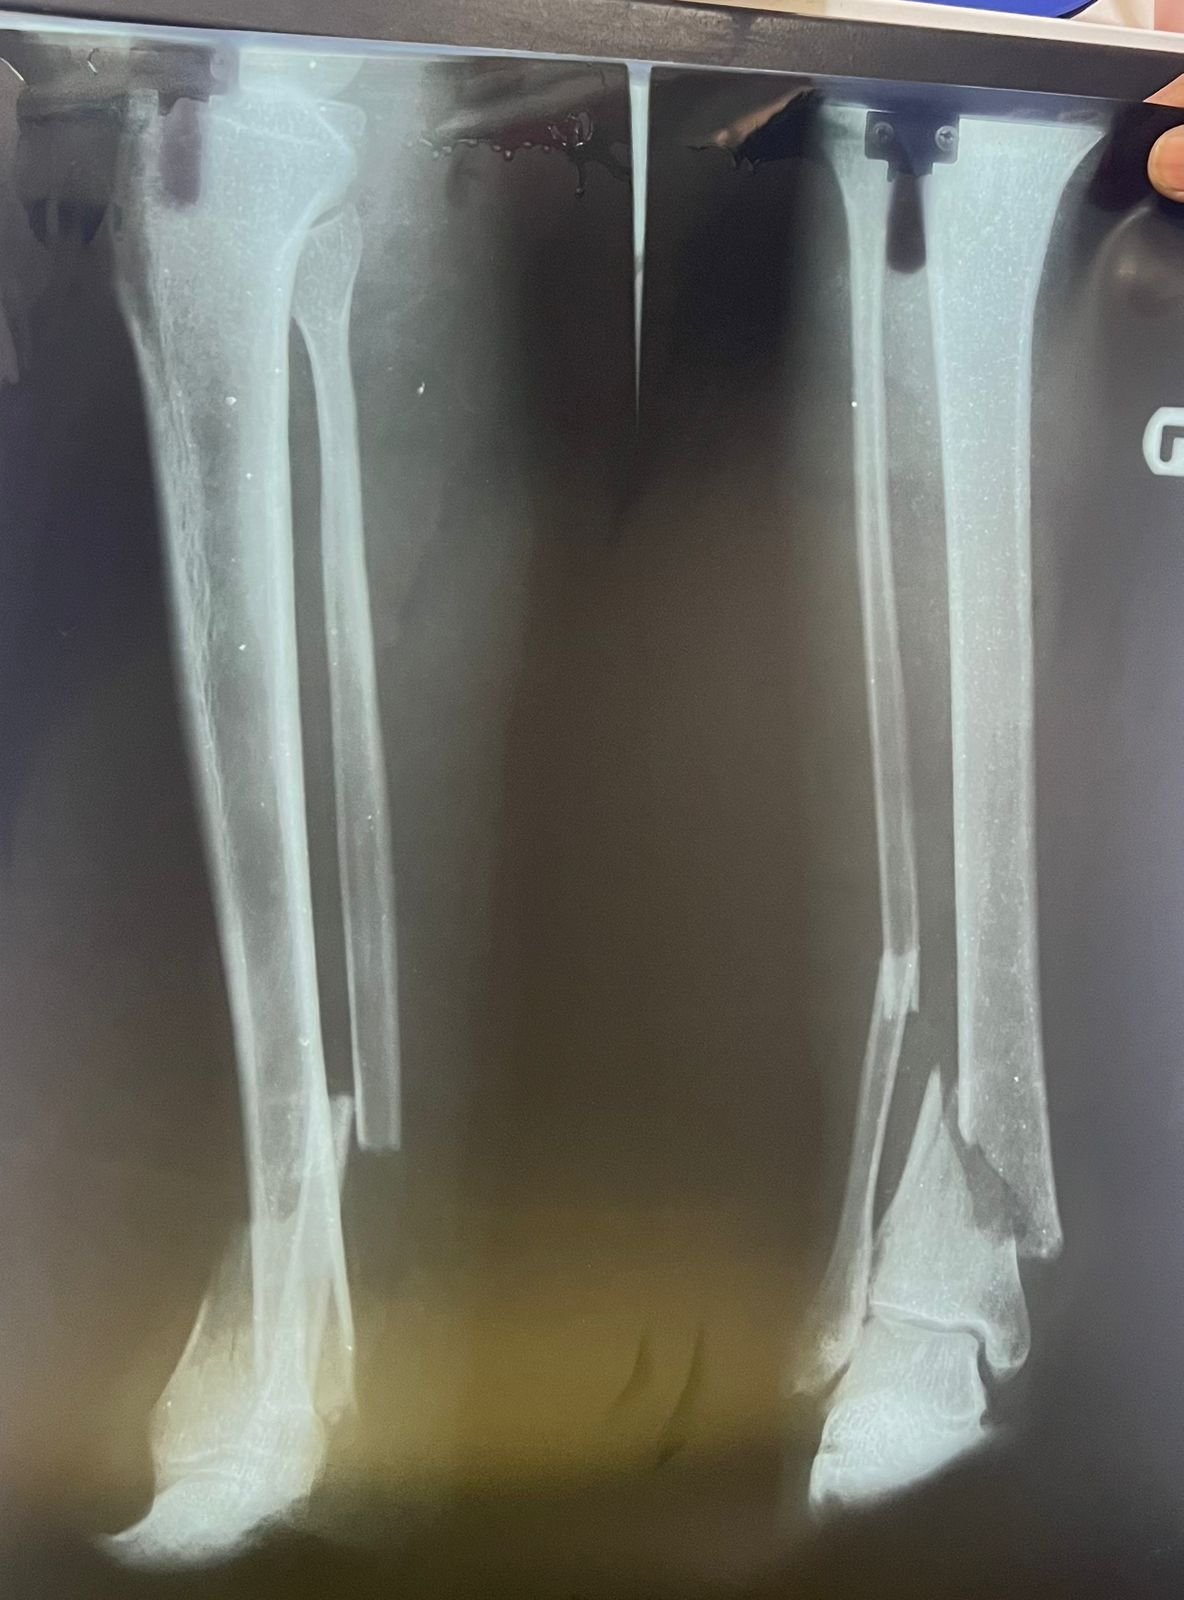

Pre op & postop X-ray compound fracture lower tibia

& fibula | Heal fracture pre & postop | Clavicle